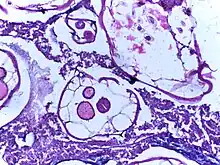

- Echinococcosis (Echinococcus infection)

- Taeniasis/cysticercosis (Taenia infection)

- Coenurosis (T. multiceps, T. serialis, T. glomerata, and T. brauni infection)